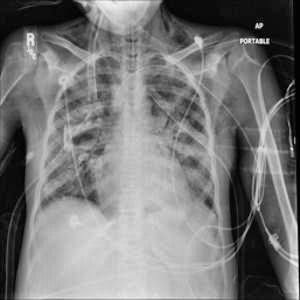

Tashxis natijasi

Bemor: Fibroz kasalligiga chalingan

Aniqlik: 0.9388282895088196%

Klass ehtimolliklari

0.0181732587516308%

0.9388282895088196%

0.0286508165299892%

0.0143477041274309%